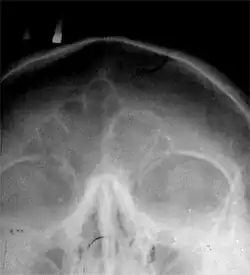

Zatoki przynosowe.

Zatoki przynosowe (łac. sinus paranasales) – przestrzenie pneumatyczne w kościach twarzoczaszki mające połączenie z jamą nosową. Są to wpuklenia błony śluzowej wrośnięte od jamy nosowej w otaczające kości, od których przyjmują swoje nazwy. Zaczynają się one rozwijać u człowieka już w życiu płodowym, ostateczne zaś wymiary osiągają w drugiej dekadzie życia[1]. W rozwoju embrionalnym jako pierwsza wykształca się zatoka szczękowa.